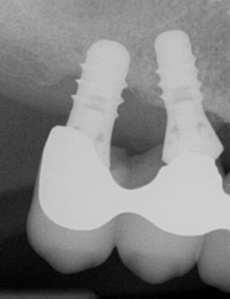

Factors related to the implant/prosthesis design and placement can also influence the risk of peri-implant disease (see figure: Poorly fitting restoration). However, aspects of surgical and prosthodontic planning, implant design, surgical implant placement and restoration are beyond the scope of this guidance and are not discussed in detail.*

Peri-implant bone loss around implants with poorly fitted and poorly seated crowns.